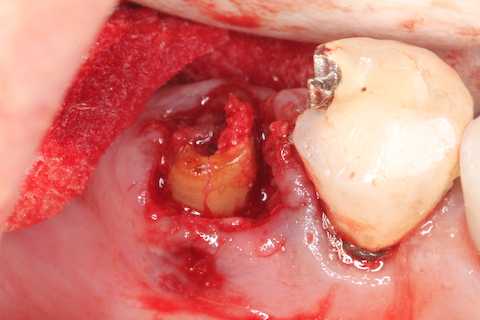

70代女性、右下5、歯根破折、歯根端肥大

抜くのに時間がかかって、歯牙だけではなく周囲の歯槽骨を始めとする組織にもダメージが大きかった。

CK部分は簡単に抜けたが

残根鉗子で掴んでもグラグラするだけで抜けない。歯根端が膨らんでいるので抜けないのだ

抜けた、、膿瘍がついてくる。疲れた

歯根端の膨らみはセメント質の肥厚だ。炎症が長年続くとこうなるということだが。

根尖が丸い。根尖口も閉じていない